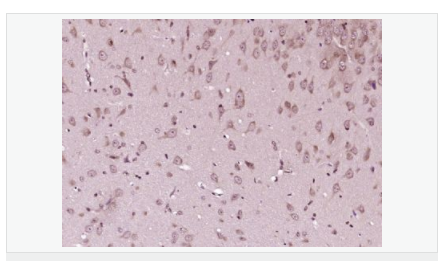

| 產(chǎn)品應(yīng)用 | WB=1:500-2000 ELISA=1:5000-10000 IHC-P=1:100-500 IHC-F=1:100-500 Flow-Cyt=1μg/Test ICC=1:100-500 IF=1:100-500 (石蠟切片需做抗原修復(fù)) not yet tested in other applications. optimal dilutions/concentrations should be determined by the end user. |

| 產(chǎn)品介紹 | This gene encodes a cyclin-dependent kinase inhibitor, which shares a limited similarity with CDK inhibitor CDKN1A/p21. The encoded protein binds to and prevents the activation of cyclin E-CDK2 or cyclin D-CDK4 complexes, and thus controls the cell cycle progression at G1. The degradation of this protein, which is triggered by its CDK dependent phosphorylation and subsequent ubiquitination by SCF complexes, is required for the cellular transition from quiescence to the proliferative state. [provided by RefSeq, Jul 2008] Function: Important regulator of cell cycle progression. Involved in G1 arrest. Potent inhibitor of cyclin E- and cyclin A-CDK2 complexes. Forms a complex with cyclin type D-CDK4 complexes and is involved in the assembly, stability, and modulation of CCND1-CDK4 complex activation. Acts either as an inhibitor or an activator of cyclin type D-CDK4 complexes depending on its phosphorylation state and/or stoichometry. Subunit: Forms a ternary compex with CCNE1/CDK2/CDKN1B. Subcellular Location: Nucleus. Cytoplasm. Endosome. Note=Nuclear and cytoplasmic in quiescent cells. AKT-or RSK-mediated phosphorylation on Thr-198, binds 14-3-3, translocates to the cytoplasm and promotes cell cycle progression. Mitogen-activated UHMK1 phosphorylation on Ser-10 also results in translocation to the cytoplasm and cell cycle progression. Phosphorylation on Ser-10 facilitates nuclear export. Translocates to the nucleus on phosphorylation of Tyr-88 and Tyr-89. Colocalizes at the endosome with SNX6; this leads to lysosomal degradation. Tissue Specificity: Expressed in all tissues tested. Highest levels in skeletal muscle, lowest in liver and kidney. Post-translational modifications: Phosphorylated; phosphorylation occurs on serine, threonine and tyrosine residues. Phosphorylation on Ser-10 is the major site of phosphorylation in resting cells, takes place at the G(0)-G(1) phase and leads to protein stability. Phosphorylation on other sites is greatly enhanced by mitogens, growth factors, cMYC and in certain cancer cell lines. The phosphorylated form found in the cytoplasm is inactivate. Phosphorylation on Thr-198 is required for interaction with 14-3-3 proteins. Phosphorylation on Thr-187, by CDK2 leads to protein ubiquitination and proteasomal degradation. Tyrosine phosphorylation promotes this process. Phosphorylation by PKB/AKT1 can be suppressed by LY294002, an inhibitor of the catalytic subunit of PI3K. Phosphorylation on Tyr-88 and Tyr-89 has no effect on binding CDK2, but is required for binding CDK4. Dephosphorylated on tyrosine residues by G-CSF. Ubiquitinated; in the cytoplasm by the KPC complex (composed of RNF123/KPC1 and UBAC1/KPC2) and, in the nucleus, by SCF(SKP2). The latter requires prior phosphorylation on Thr-187. Ubiquitinated; by a TRIM21-containing SCF(SKP2)-like complex; leads to its degradation. DISEASE: Defects in CDKN1B are the cause of multiple endocrine neoplasia type 4 (MEN4) [MIM:610755]. Multiple endocrine neoplasia (MEN) syndromes are inherited cancer syndromes of the thyroid. MEN4 is a MEN-like syndrome with a phenotypic overlap of both MEN1 and MEN2. Similarity: Belongs to the CDI family. SWISS: P46527 Gene ID: 1027 Database links: Entrez Gene: 1027 Human Entrez Gene: 12576 Mouse Omim: 600778 Human SwissProt: P46527 Human SwissProt: P46414 Mouse Unigene: 238990 Human Unigene: 2958 Mouse Important Note: This product as supplied is intended for research use only, not for use in human, therapeutic or diagnostic applications. P27蛋白是一種新發(fā)現(xiàn)的周期素依賴激酶抑制劑,屬于細(xì)胞周期的負(fù)性調(diào)控因子。P27基因及其產(chǎn)物的異常表達(dá)可能與某些腫瘤的發(fā)生、發(fā)展有著密切的關(guān)系。P27蛋白對細(xì)胞周期的調(diào)控及在腫瘤中發(fā)揮著很重要的作用。 |